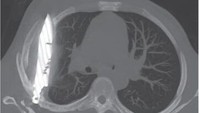

Tujuh hari pasca operasi, foto rontgen dada menunjukkan adanya chest tube atau selang dada yang masih terpasang dan opasifikasi paru. Selang dada dilepas pada hari kedelapan dan kondisi pasien berangsur-angsur membaik. (Foto: Journal of Surgical Case Reports)